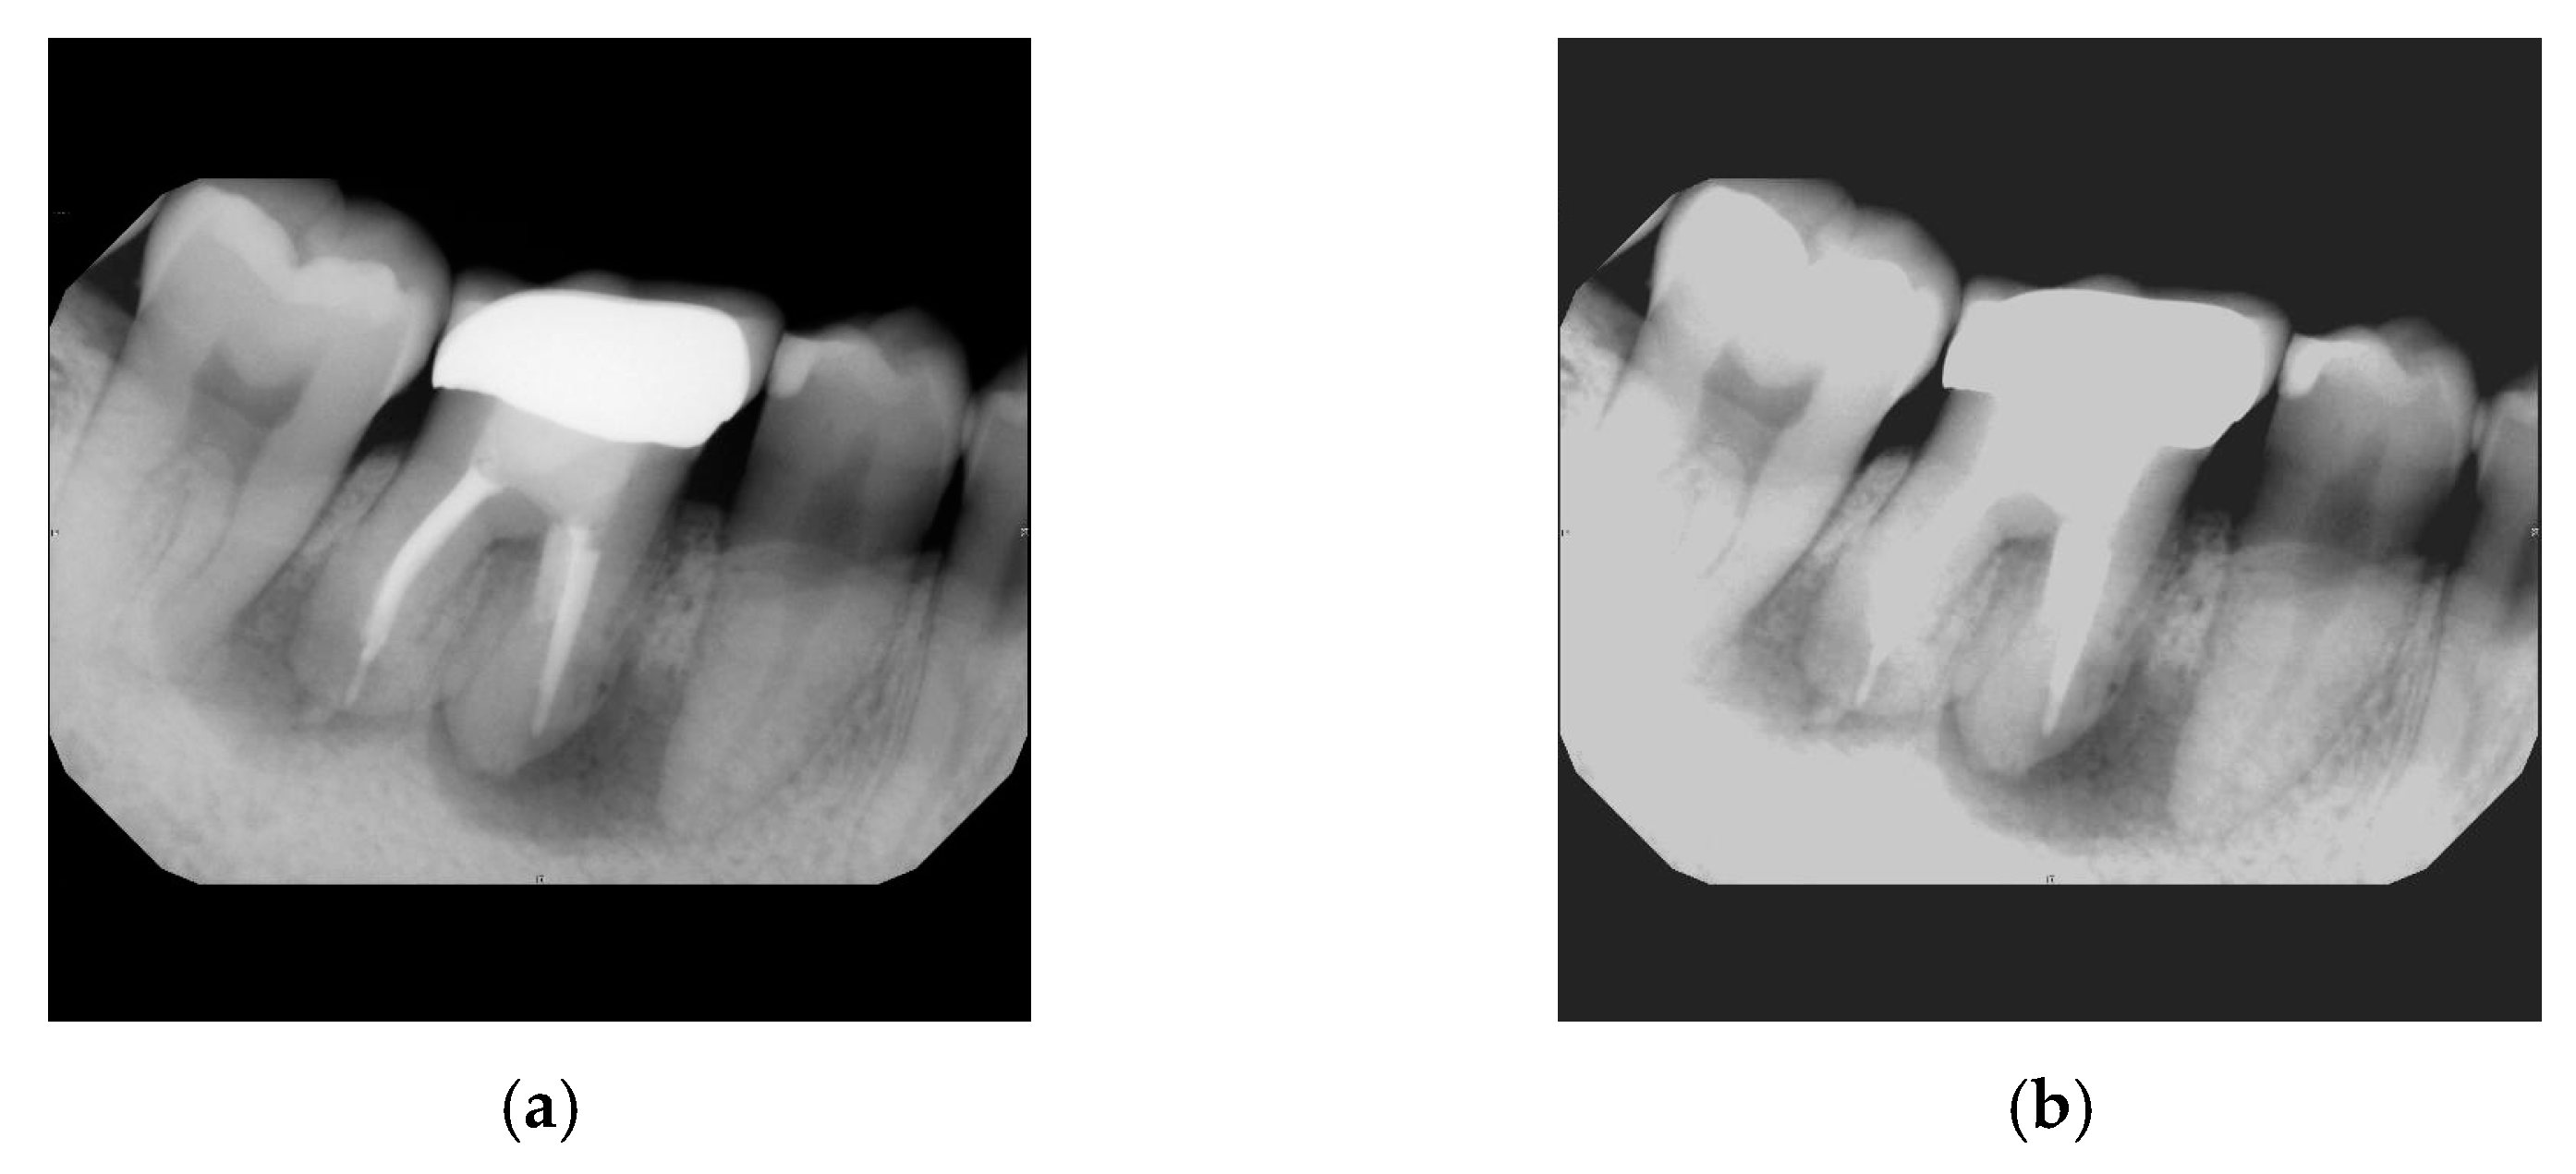

- Aspect 3: Expanding the Cropping Range